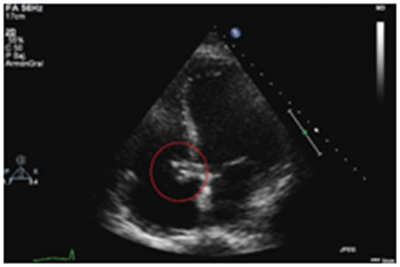

With the diagnosis of Gerbode defect (LV to RA shunt) due to bacterial endocarditis a coronary angiography was done to rule out the presence of coronary disease before cardiac surgery. The aortography showed contrast across the LV to the RA (Figure 3). Streptococcus anginosus was isolated in blood cultures starting antibiotic treatment with ceftriaxone and daptomycin. The patient underwent surgery with cryopreserved homograft implantation of the aortic root with reimplantation of the coronary arteries. After cardiac surgery the patient developed postcardiotomy cardiogenic shock requiring aortic counterpulsation ballon and advanced mechanical circulatory support with veno-arterial extracorporeal membrane oxygenation (VA ECMO)

Figure 3 Aortography showing the pass of contrast from the ascending aorta and left ventricle (LV) to the right atrium (RA).